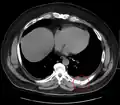

Radiographie du gril costal ou thorax osseux

Techniquement, il s'agit de mettre en évidence la partie osseuse du thorax, en modifiant l’exposition de la radiographie. L'indication est la mise en évidence de fracture de côte.

Si cette technique est très spécifique (100 %[1]), elle est peu sensible (15 %[1]). En pratique elle est moins utilisée que la radiographie standard en cas de suspicion de fracture costale et ce pour deux raisons :